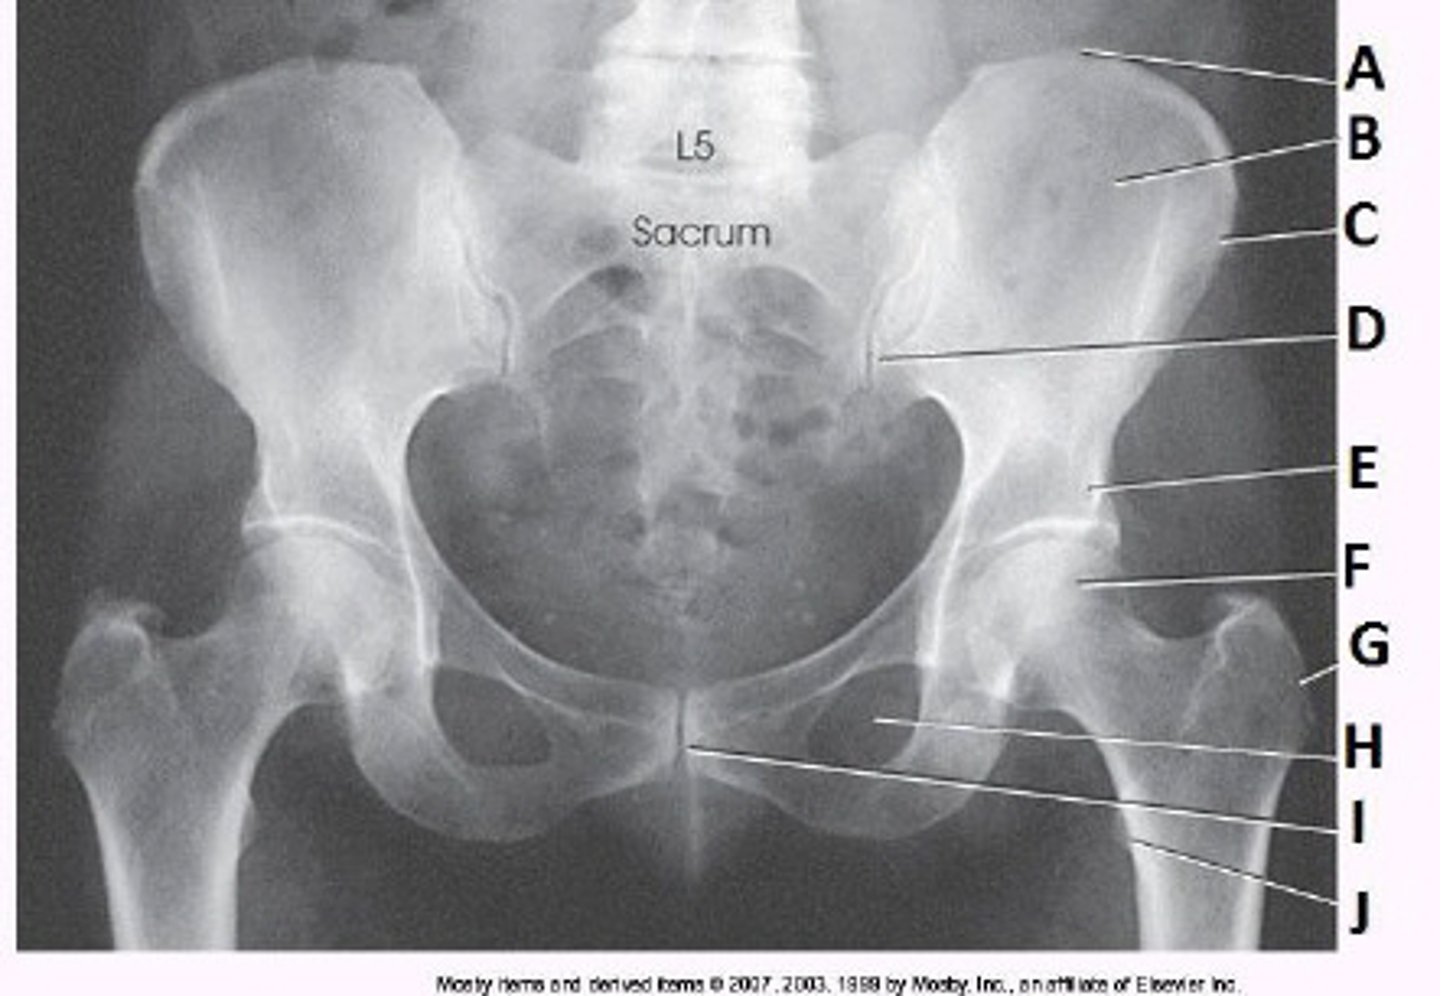

ASIS

What anatomy is labeled as letter C in the image below?

Iliac crest

Ala of ilium

AIIS

Acetabulum

What anatomy is labeled as letter A in the image below?

Femoral head

Femoral neck

Greater trochanter

The lower limbs were not internally rotated.

What positioning error is evident in the image below?

None. This image meets all evaluation criteria for this projection.

The lower limbs were not externally rotated.

The knees were not flexed to reduce lordotic curve.